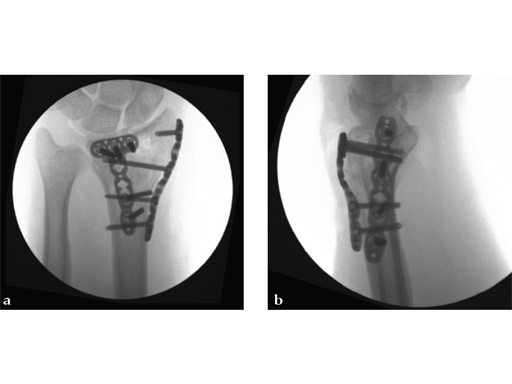

Case 2: A 44-year-old man sustained polytrauma following a car accident. Among his injuries was a distal radial fracture, Mller AO Classification 23-C1.

Case provided by Vitezslav Ruber, Brno, Czech Republic